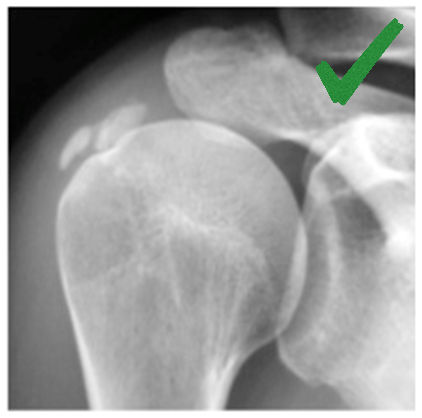

Ακτινολογική ταξινόμηση της ασβεστοποίησης στον ώμο (Gartner and Hayer)

Ανάλογα με την απεικόνιση στην ακτινογραφία ταξινομείτε ως εξής:

| Τύπος Ι : Ομαλά όρια, αυξημένη πυκνότητα ασβέστωσης. Φάση σχηματισμού | Τύπος ΙΙ: Σχήμα ομαλό, πυκνό ή οξύ, περιοχές ακτινοδιαπερατές. Φάση σταθεροποποίησης | Τύπος ΙΙΙ: Διάφανη, νεφελώδης εμφάνιση, χωρίς σαφή όρια. Φάση απορρόφησης |